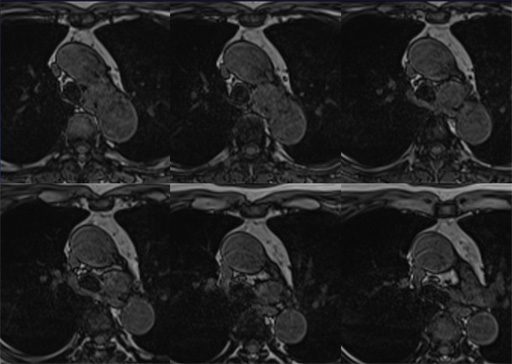

図8 MRI T1WI (out of phase) 図9 MRI T2WI

図9 MRI T2WI 図10 MRI fat sat T2WI

図10 MRI fat sat T2WI 図11 MRI fat sat T1WI

図11 MRI fat sat T1WI